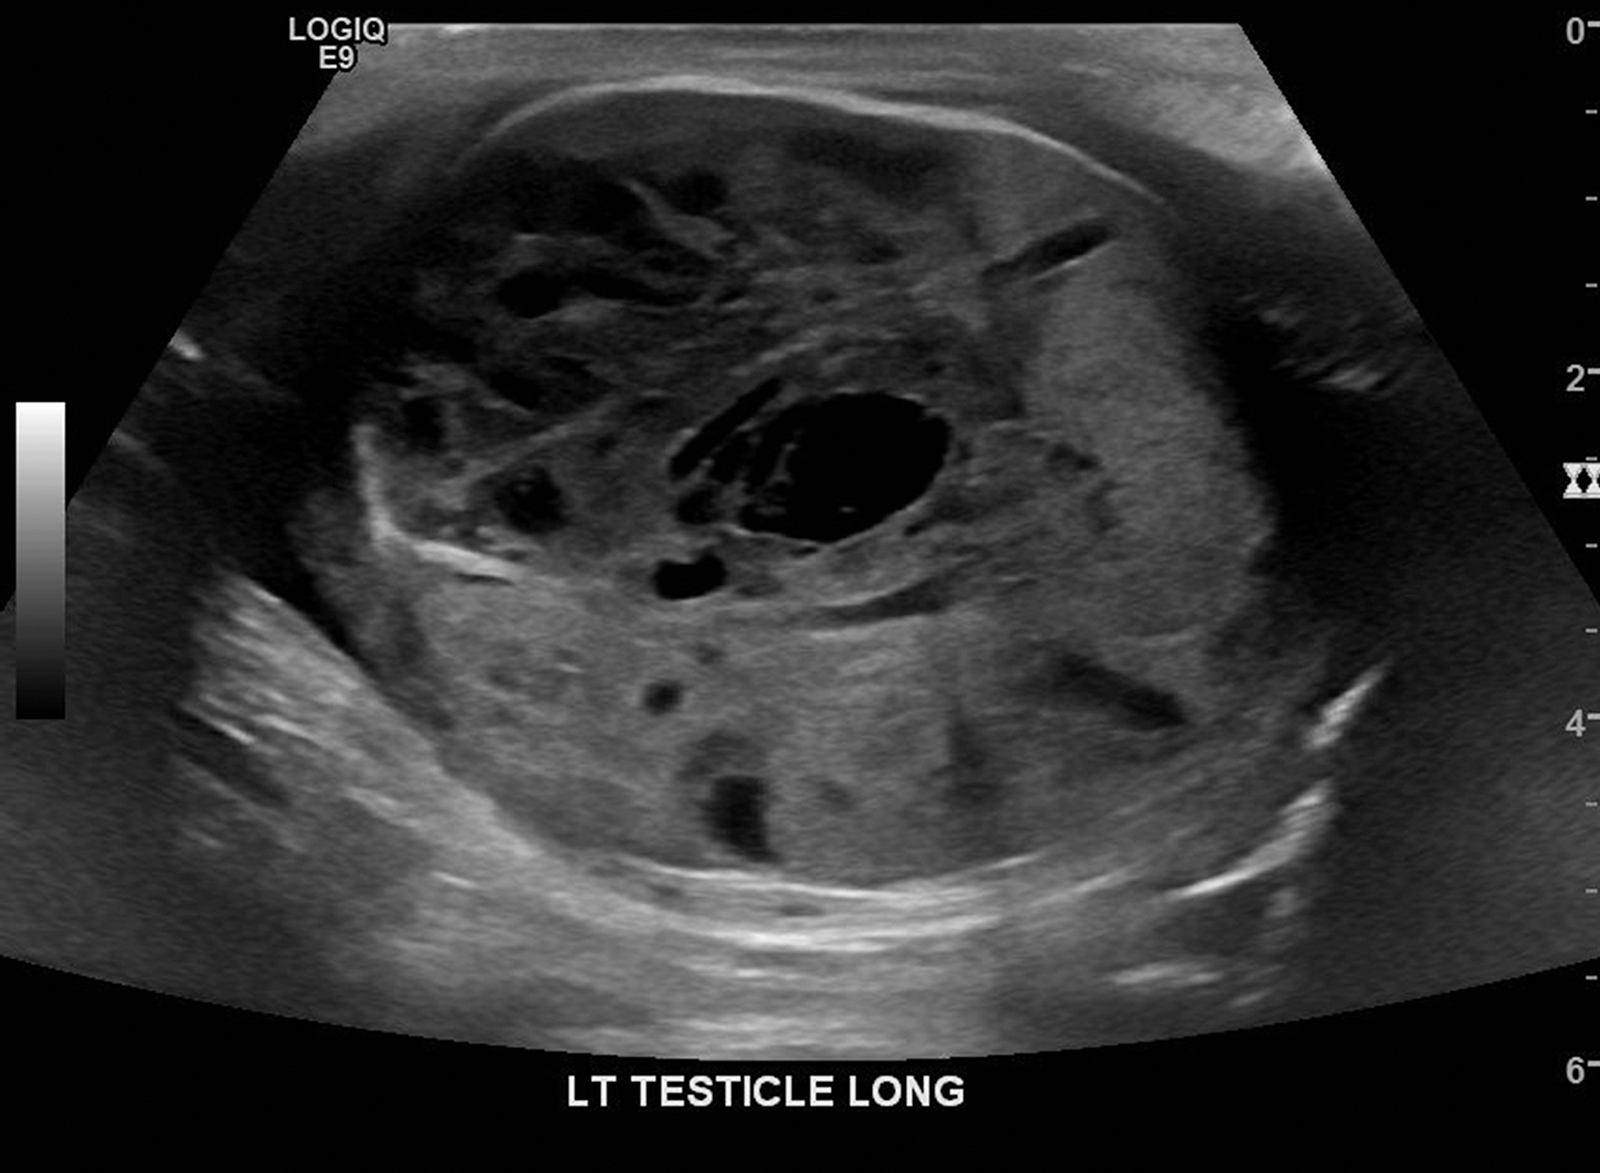

A 50-year-old man with a painless, palpable mass in his left testicle was referred to the urology clinic. He had a history of Crohn disease that was managed with bowel resection but was otherwise previously healthy. He reported that the testicle mass was firm and hard, nontender, and had been present for about 1 month with no associated symptoms. Ultrasonographic image of the testicle demonstrated complex marked heterogeneous echotexture with cystic and solid components and prominent vascularity consistent with neoplasm (Figure 1). The right testicle was normal. Serum human chorionic gonadotropin was in the normal range at less than 1.0 mIU/mL, and α-fetoprotein (AFP) was elevated at 9.4 ng/mL. At this time, the mass was considered a probable nonseminomatous germ cell tumor. Computed tomography (CT) of the abdomen and pelvis revealed a left testicular mass consistent with testicular cancer without adenopathy or metastatic disease. Radical orchiectomy was performed 5 days after presentation without complication.

Longitudinal ultrasonographic image of the left testicle showing the majority of the testicle encompassed by a heterogeneous complex hypervascular mass with cystic and solid components consistent with large neoplasm.